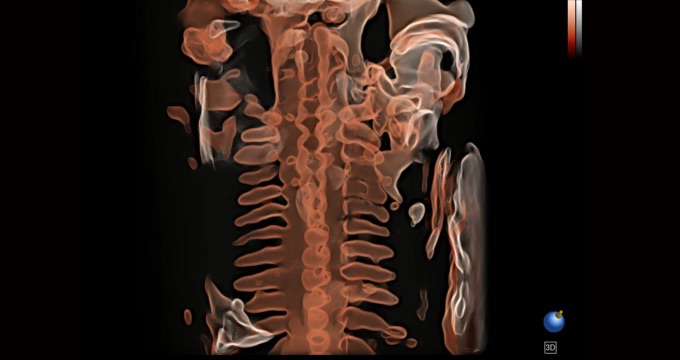

三维光影成像技术采用新型的渲染方式,增强边缘信息,使得轮显示清晰完整,为临床提供丰富、直观的三维结构,提供临床诊断准确性。